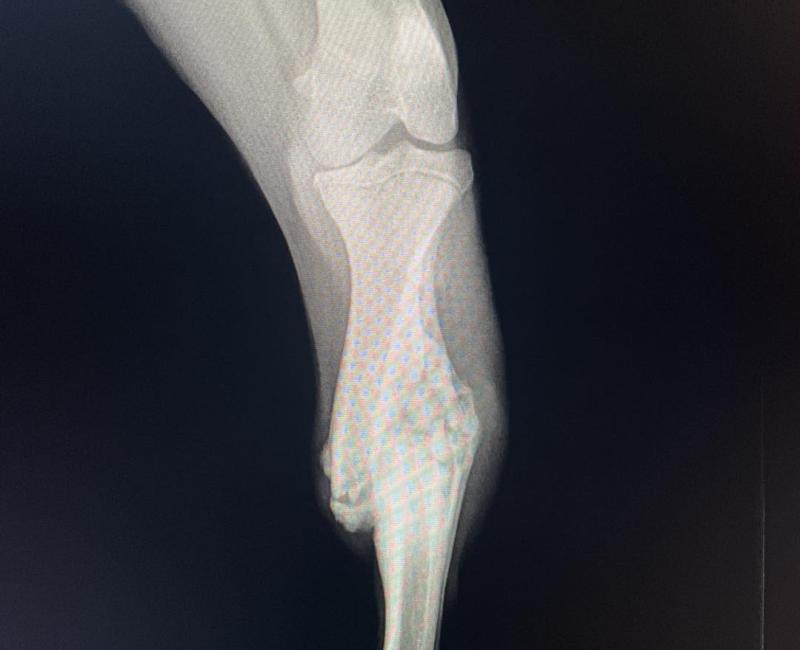

Es un joven perrito, simpático, cariñoso, alegre,….Le observamos que tenía un bulto raro en una pata, estábamos seguros que era una fractura antigua ya soldada. Tras pasar por el veterinario y realizar radiografías, nos confirmaron que tenia una fractura de tibia y peroné, sobrepuesto y totalmente soldado. La veterinaria ha evaluado la situación y, ya que solo ha perdido un par de centímetros en comparación con la otra pata, se ha decidido no tocarle puesto que no cojea, corre, salta….y tocando es posible que quede peor.